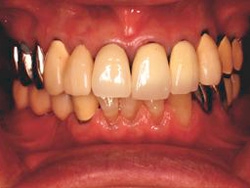

両側5歯症例

両側5歯症例両側5歯症例両側5歯症例 主訴-義歯のバネが壊れて手前の歯が痛んできた。 術前(旧義歯装着、鏡像) 術前(下顎粘膜面、鏡像)術前(下顎粘膜面、鏡像)術前(下顎粘膜面、鏡像) 術前レントゲン術前レントゲン術前レントゲン 術前口腔内(正面観)術前口腔内(正面観)術前口腔内(正面観)

術後(鏡像)術後(鏡像)術後(鏡像) 術後口腔内(正面観)術後口腔内(正面観)術後口腔内(正面観)もう入れ歯は要らなくなりました。 術後レントゲン術後レントゲン術後レントゲン